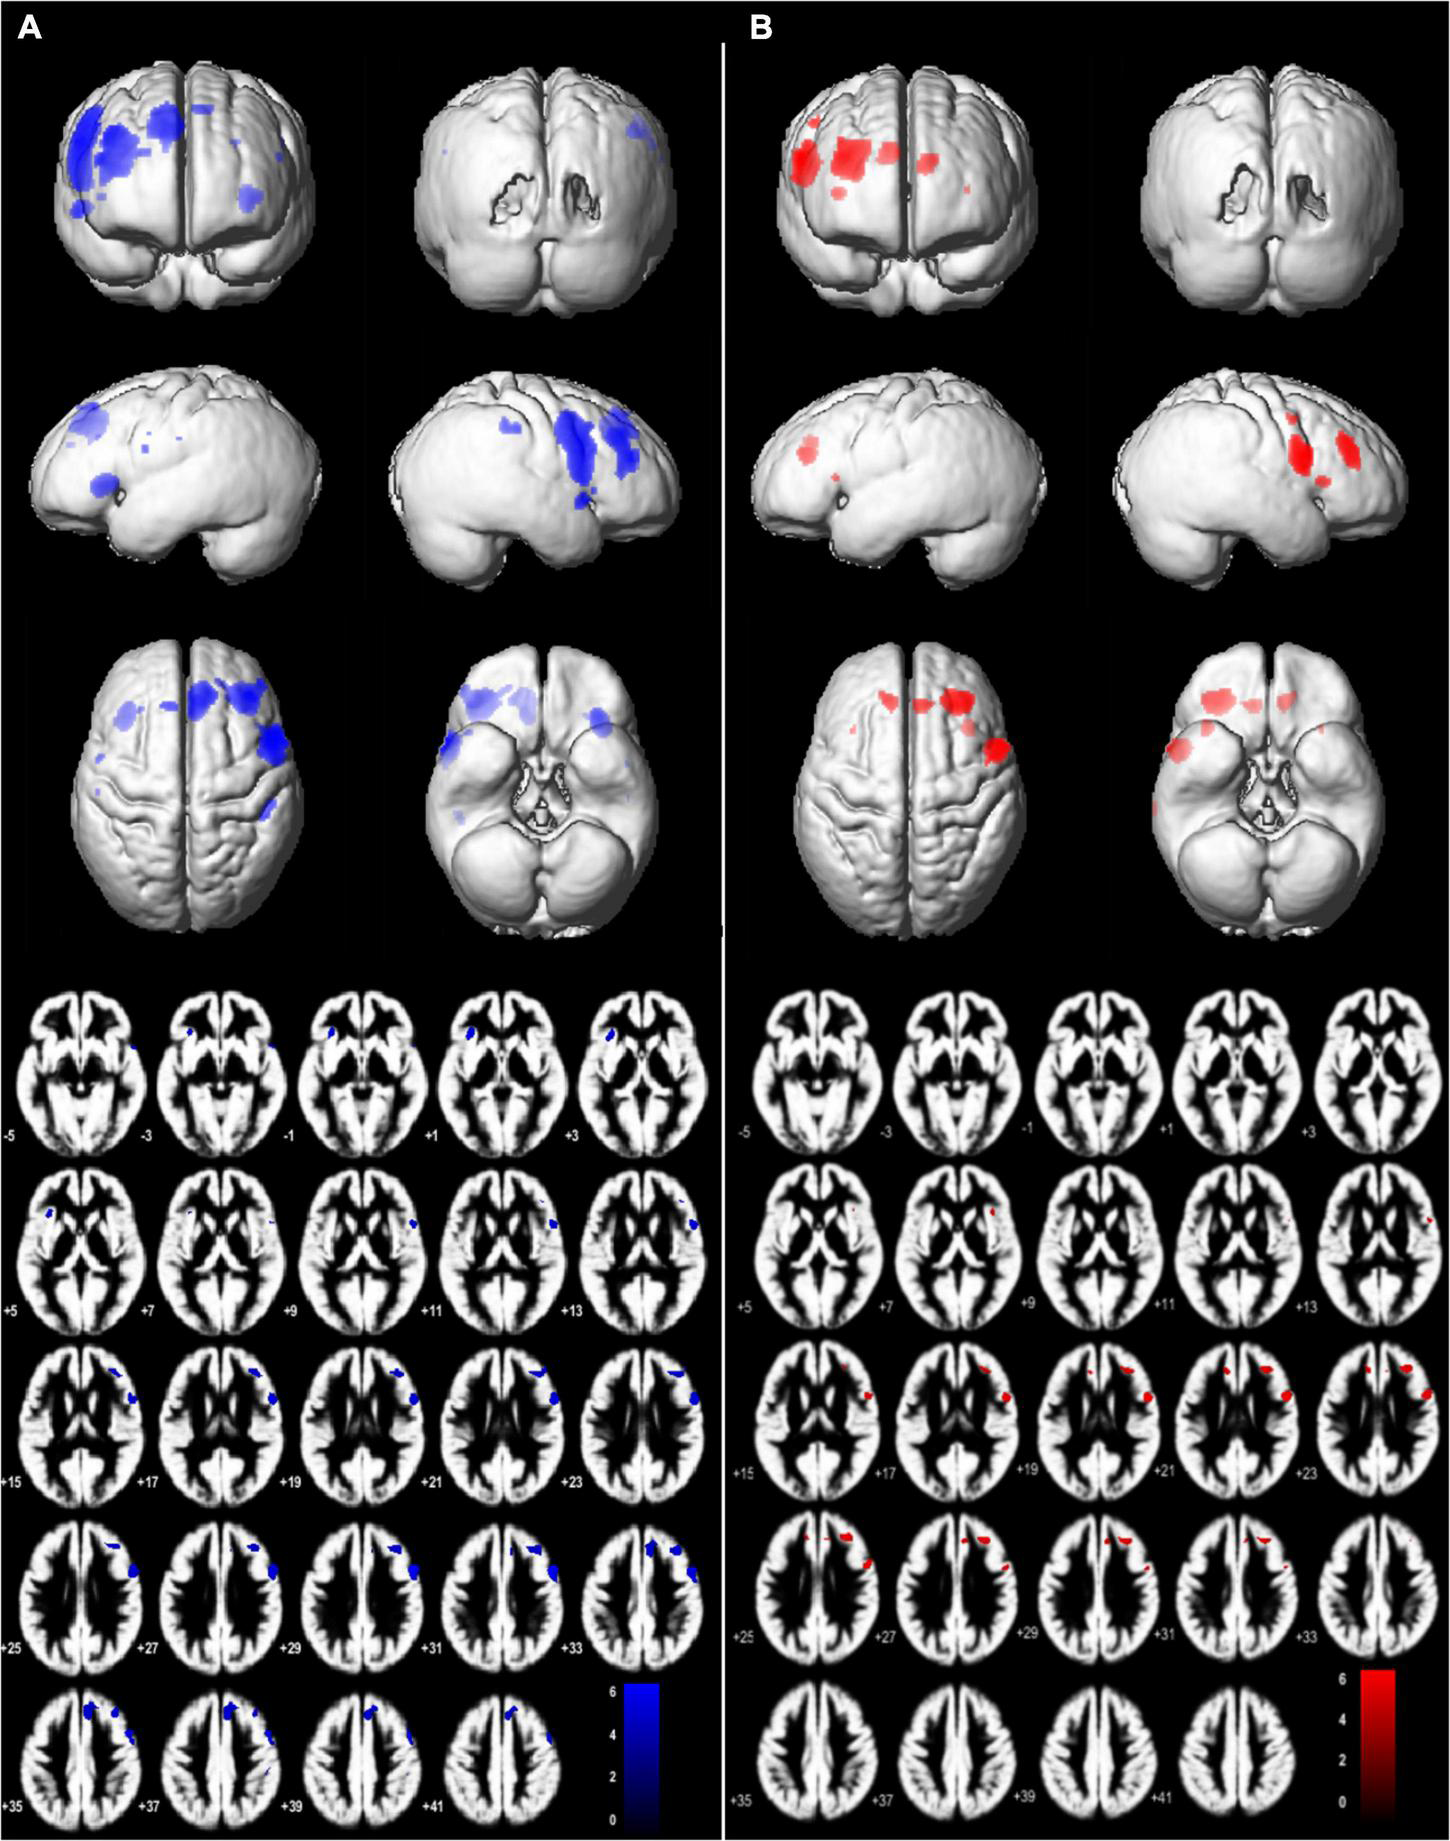

The JPS condition evoked significantly greater BOLD response (P = 0.05, FWE corrected; voxel limit 15) in seven brain regions for each leg compared to the Flex condition without a JPS task. These included prefrontal regions, the precentral gyrus, cingulate gyri and insula (see Figures 3, 4 and Table 2 for all significant regions with voxel extent, exact statistics, and MNI coordinates).

FIGURE 3

Brain regions with significant main effect condition in (JPS > Rest) > (Flex > Rest), P = 0.05, family-wise corrected, voxel limit 15. Slices –5:2:38 mm (MNI) in inferior-superior direction are shown. Group mean brains (Dartel) are used for the illustration for (A) left-side analyses – L-ACLR moving their injured left leg and CTRL moving their left non-dominant leg, and (B) right-side analyses – R-ACLR moving their right injured leg and CTRL moving their right non-dominant leg.

Between-Group Comparisons of Brain Response During the Knee Joint Position Sense Test

No significant between-group differences were found on the corrected level (FWE 0.05).